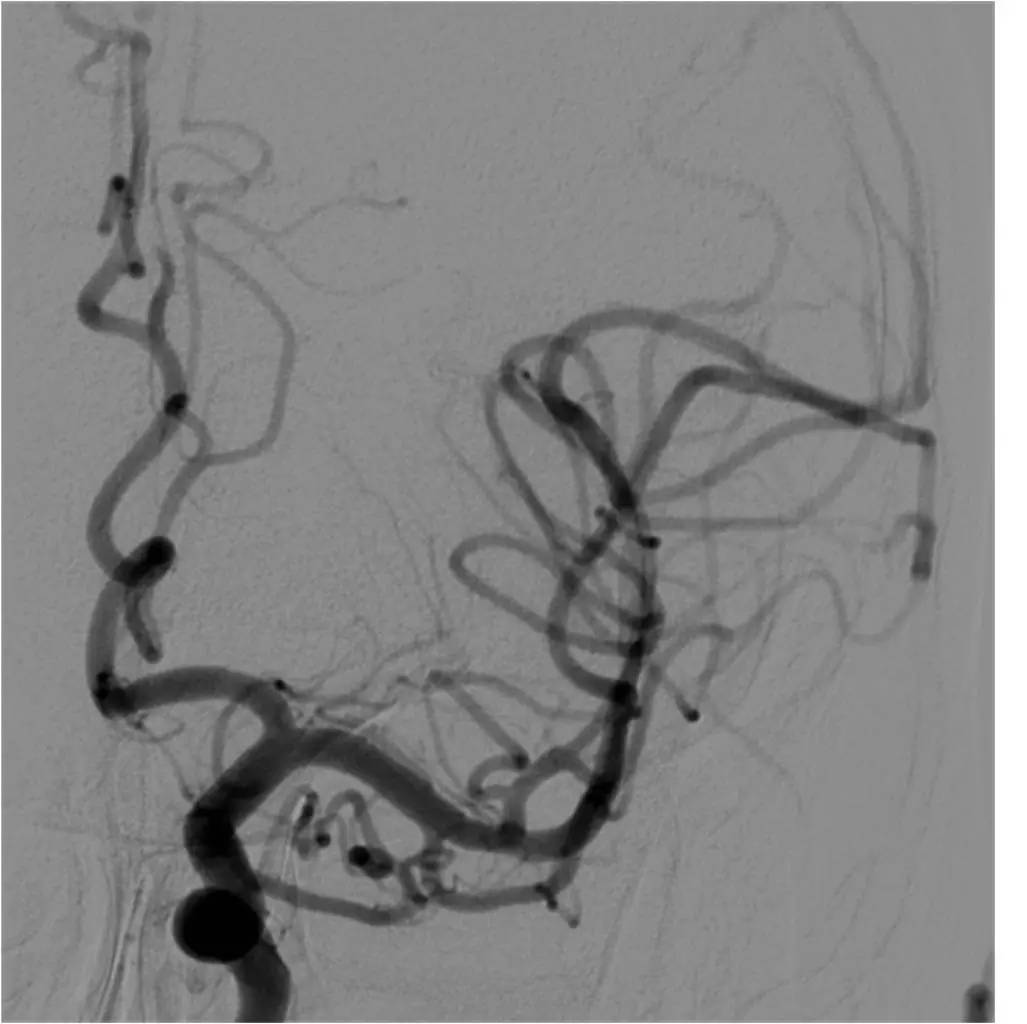

》男性,43岁,头痛、头晕伴发作性意识不清10余天入院。脑电图异常,查体无阳性体征。入院诊断“病毒性脑炎”。

》入院第3天,突发混合型失语伴右侧肢体活动不灵。

》头MRI+MRA:左侧岛叶斑片状异常信号,左侧颈内动脉不显影,左侧大脑中动脉显影较淡,远端分支较少。

》重点脑血管造影

》全麻下手术

》术后C臂CT无出血

》术后20小时复查头颅CT无出血。